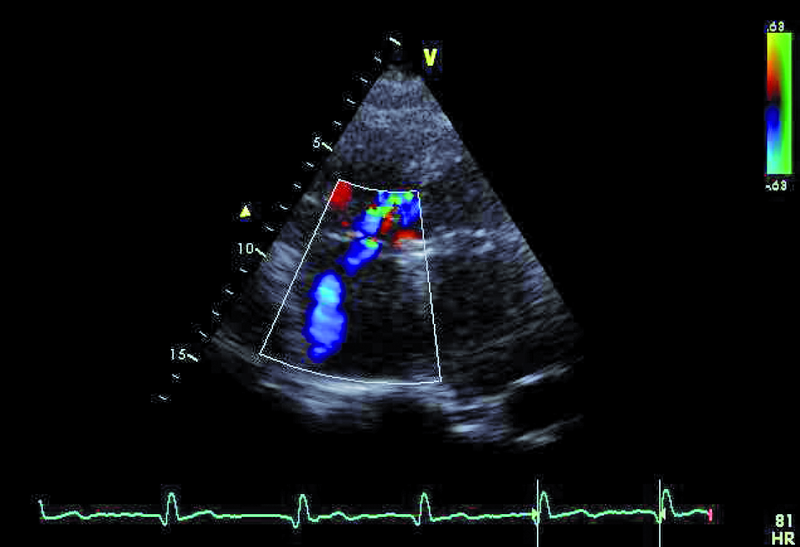

2. Istotna niedomykalność zastawki mitralnej (ryc. 2).

4. Mała niedomykalność zastawki trójdzielnej (ryc. 4-6).

5. Mały ubytek przegrody międzykomorowej z lewo-prawym przeciekiem (ryc. 5).

6. Istotne nadciśnienie płucne (ryc. 6).